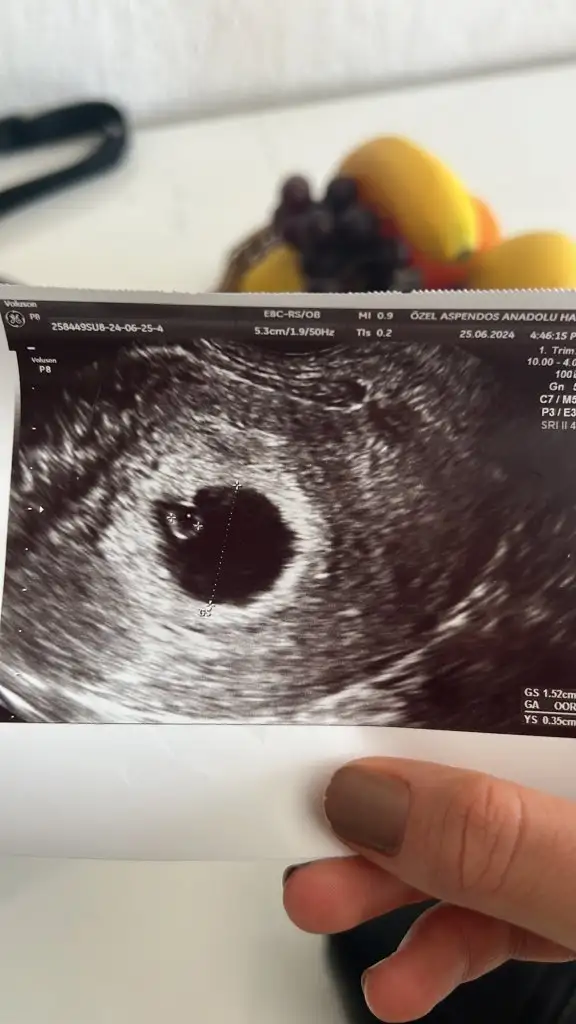

9 haftalik gebeyim adete gore ultrasonda 6 cikdi gec dollenmemi bos gebelikmi

Bana kurtaj dedi ayrintili ultrason istedi bebek yok kese 43 mm suan kan verdim bekliyorum

seninle aynı durumdayım suan bende doktor kürtaj dedi sat a göre 7+5 kese büyüklüğüne göre geç döllenme imkansız dedi embriyo gelişmemiş dedi çarşambaya bende kürtaj olacağım gerçekten çok zor hala belirtileri yasayip bebeğinin öldügünü bilmek 😔

Eki Görüntüle 3445715 seninle aynı durumdayım suan bende doktor kürtaj dedi sat a göre 7+5 kese büyüklüğüne göre geç döllenme imkansız dedi embriyo gelişmemiş dedi çarşambaya bende kürtaj olacağım gerçekten çok zor hala belirtileri yasayip bebeğinin öldügünü bilmek 😔

Doktor bebeğin bu olduğunu söyledi ve maalesef gelişmemiş dedi yarına 8+3 oluyor gelişmesi durmuş tek tas şeklinde olması gerekiyormuş yarın başka bir doktora gideceğim ama görüntü aynı şekil olursa ki büyük ihtimal öyle olacak çarşambaya kürtaj olacağım 😔